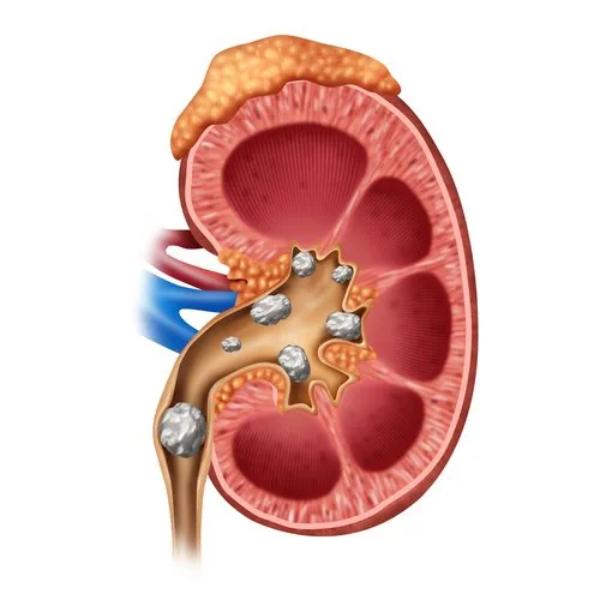

Best Kidney Stone Surgeon in Thane – Advanced Lase...

Kidney Stone Removal in Thane – Safe & Effective P...

Kidney Stone Removal Treatment in Siddharth Nagar,...

Top-Rated Kidney Stone Surgeon Near Me in Veer Sav...

Best Treatments for Kidney Stones at Our Clinic Ki...

Best Kidney Stone Treatment in Thane West – Non-Su...

Kidney Stone Pain in Thane – Advanced Treatment fo...

Exploring Advanced Urology Procedures in Thane Wes...